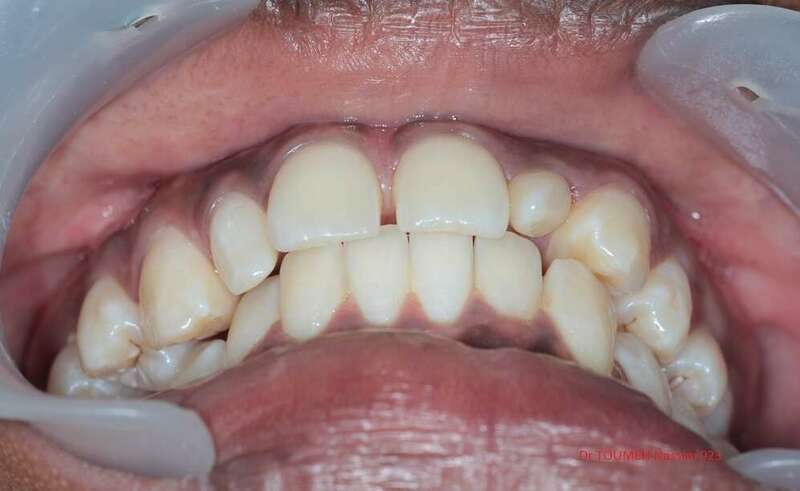

Latérales naines et orthodontie

la forme des dents influence grandement l’esthétique du sourire

La malformation des incisives latérales en est l'illustration

Le traitement consiste à redresser les dents à l'aide d'un appareil orthodontique (Multiattaches) et à redonner une forme normale aux dents malformées.

Dans ce cas présenté des couronnes provisoires en résines ont été posées.

Avant